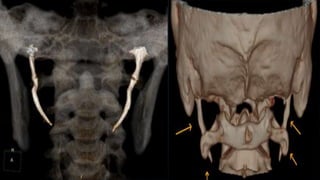

• Final diagnosis :- Based on subjective data & objective data [ CT scan of neck ]

obtained from the patient is assessed to have " Eagle's Syndrome "

• Ct scan of neck :-

1. Mucosal thickening of b/l maxillary sinus with obliterated right osteomeatal

complex

2. Elongated styloid process b/l [ Right – 4.48 cm , Left – 4.41 cm ]

ASSESSMENT • Provisional diagnosis:- Globus hystericus • Final diagnosis :- Based on subjective data & objective data [ CT scan of neck ] obtained from the patient is assessed to have " Eagle's Syndrome "